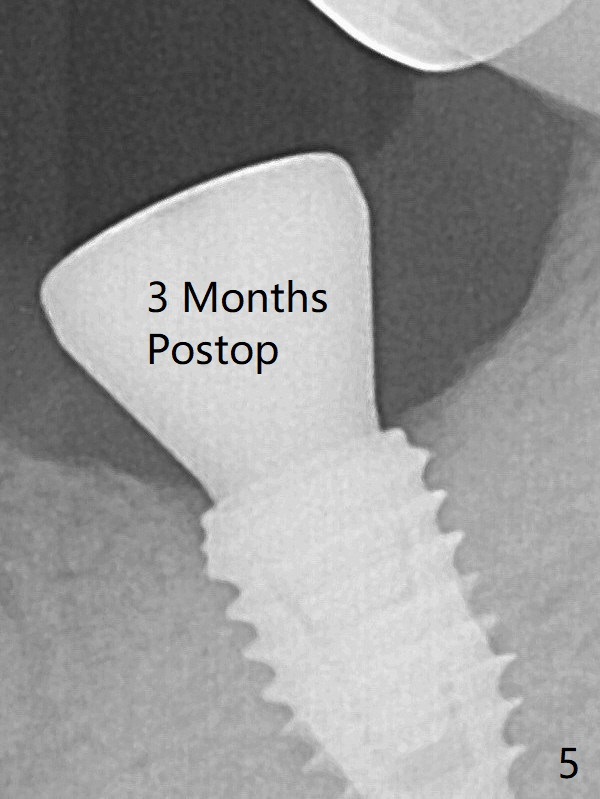

According to drill sequence at #19, the osteotomy is over prepared with the 4.5x8.5 mm last drill.  The bone density does not feel so high that warrants use of 5.0 mm cortical tap.  The insertion torque is ~ 25 Ncm (Fig.1).  When a 6x4 mm healing abutment is placed, the implant does not turn.  The distobuccal gingiva is slightly torn; following packing autogenous bone (<), periodontal dressing is applied.  A provisional is not fabricated at #19, considering short healing time (Fig.5).  But there is no gap between the implant  and surrounding bone, as compared to Fig.1.  It appears that overprep helps healing.